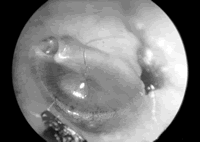

鼓室图可辅助诊断婴幼儿中耳积液

美国匹兹堡儿童医院Smith等的一项研究表明,<3岁婴幼儿鼓室压测量结果有助于诊断中耳积液。

研究者对6350例中耳积液患儿进行了规律地观察和评估,并对其中3686名儿童的鼓室压测量结果与耳镜诊断结果进行了比较,分别根据鼓室压的峰值、峰压和波形宽度对鼓室图进行分类,再将其与诊断进行比较。

结果显示,鼓室图波形的峰值越低、基底越宽,与中耳积液的关系就越密切,当鼓室压为负时,中耳积液的可能性更大。当≥6个月的患儿鼓室压测量值>0.6 ml时,仅有2.7%的患儿被诊断为中耳积液,而有80.2%的鼓室图波形平坦者被诊断为中耳积液。在<6个月的婴儿中,鼓室图与中耳积液虽然也有类似的关联,但相关性不强。≥6个月的中耳积液患儿鼓室压力特征性曲线的系数为0.84,将该数学模型用于另一组≥6个月中耳积液患儿的诊断时效果良好,这提示可将其用于其他未经选择的患者群体。[Pediatrics 2006, 118(1): 1]

研究提示:对6~35个月的婴幼儿,可结合鼓室图检查结果评估其患中耳积液的可能性。, http://www.100md.com